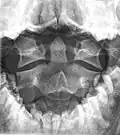

In anatomy, the axis (from Latin axis, "axle") is the second cervical vertebra (C2) of the spine, immediately inferior to the atlas, upon which the head rests. The spinal cord passes through the axis.

The defining feature of the axis is its strong bony protrusion known as the dens, which rises from the superior aspect of the bone.

The dens, also called the odontoid process, or the peg, is the most pronounced projecting feature of the axis. The dens exhibits a slight constriction where it joins the main body of the vertebra. The condition where the dens is separated from the body of the axis is called os odontoideum and may cause nerve and circulation compression syndrome.[1] On its anterior surface is an oval or nearly circular facet for articulation with that on the anterior arch of the atlas. On the back of the neck, and frequently extending on to its lateral surfaces, is a shallow groove for the transverse atlantal ligament which retains the process in position. The apex is pointed and gives attachment to the apical odontoid ligament. Below the apex, the process is somewhat enlarged and presents on either side a rough impression for the attachment of the alar ligament; these ligaments connect the process to the occipital bone.